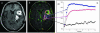

Imaging in patients with brain tumors aims toward the determination of the localization, extend, type, and malignancy of the tumor. Imaging is being used for primary diagnosis, planning of treatment including placement of stereotaxic biopsy, resection, radiation, guided application of experimental therapeutics, and delineation of tumor from functionally important neuronal tissue. After treatment, imaging is being used to quantify the treatment response and the extent of residual tumor. At follow-up, imaging helps to determine tumor progression and to differentiate recurrent tumor growth from treatment-induced tissue changes, such as radiation necrosis. A variety of complementary imaging methods are currently being used to obtain all the information necessary to achieve the above mentioned goals. Computed tomography and magnetic resonance imaging (MRI) reveal mostly anatomical information on the tumor, whereas magnetic resonance spectroscopy and positron emission tomography (PET) give important information on the metabolic state and molecular events within the tumor. Functional MRI and functional PET, in combination with electrophysiological methods like transcranial magnetic stimulation, are being used to delineate functionally important neuronal tissue, which has to be preserved from treatment-induced damage, as well as to gather information on tumor-induced brain plasticity. In addition, optical imaging devices have been implemented in the past few years for the development of new therapeutics, especially in experimental glioma models. In summary, imaging in patients with brain tumors plays a central role in the management of the disease and in the development of improved imaging-guided therapies.